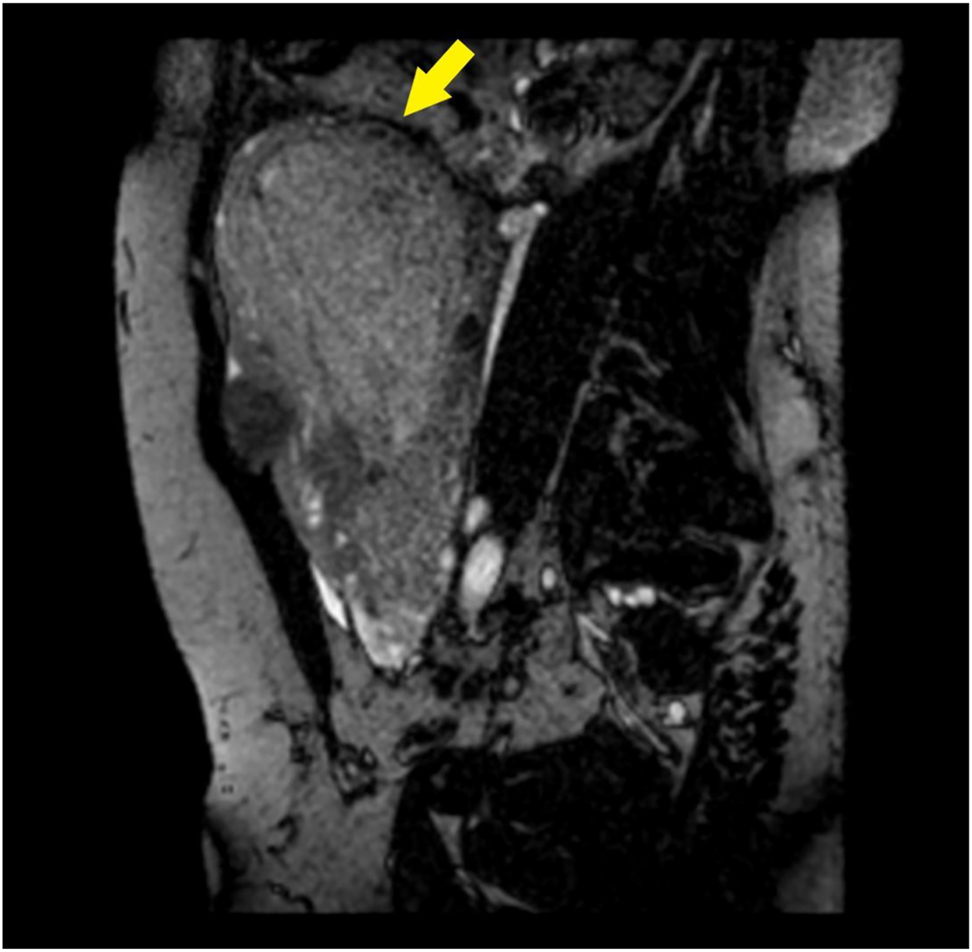

The patient was transferred by ambulance to our tertiary care center after 2 h from delivery; normal vital signs were registered during transfer and upon arrival at our emergency department, and vaginal bleeding was absent. A Foley catheter was placed with an output of 300 mL of clear urine. She was started on antibiotic prophylaxis with amoxicillin/clavulanate 875/125 mg i.v. q8hr because of mild leukocytosis and C-reactive protein (CRP) elevation (Table 1). TVS and TAS showed an increased uterine size, with multiple (>4) fibroids with the largest diameter of 120 mm, and a retained placenta. A thorough sonographic examination of the placenta was difficult because of the presence of uterine fibroids, obesity, and a posterior placenta. However, we suspected an area of myometrial invasion in the posterior uterine wall, where the placenta showed irregular margins, loss of the retroplacental clear space, myometrial thinning, and increased color doppler signal (Figures 1 and 2, Supplementary Material, Videoclip 1 [Grayscale TVS showing a posterior area of placental accretism]). To confirm the diagnosis, we asked for gadolinium-enhanced MRI. T1- and T2-weighted scans showed a diffusely enlarged uterus, with pregnancy-induced myometrial hypertrophy and irregular uterine contours, due to the presence of both intramural and subserous myomas. MRI confirmed the placental invasion of the myometrium in a posterior area extending about 60 mm, apparently without serosal infiltration (Figures 3 and 4).

Contrast-enhanced MRI.

Para-sagittal BFFE acquisition: the placenta causes marked thinning of the myometrium (arrow).